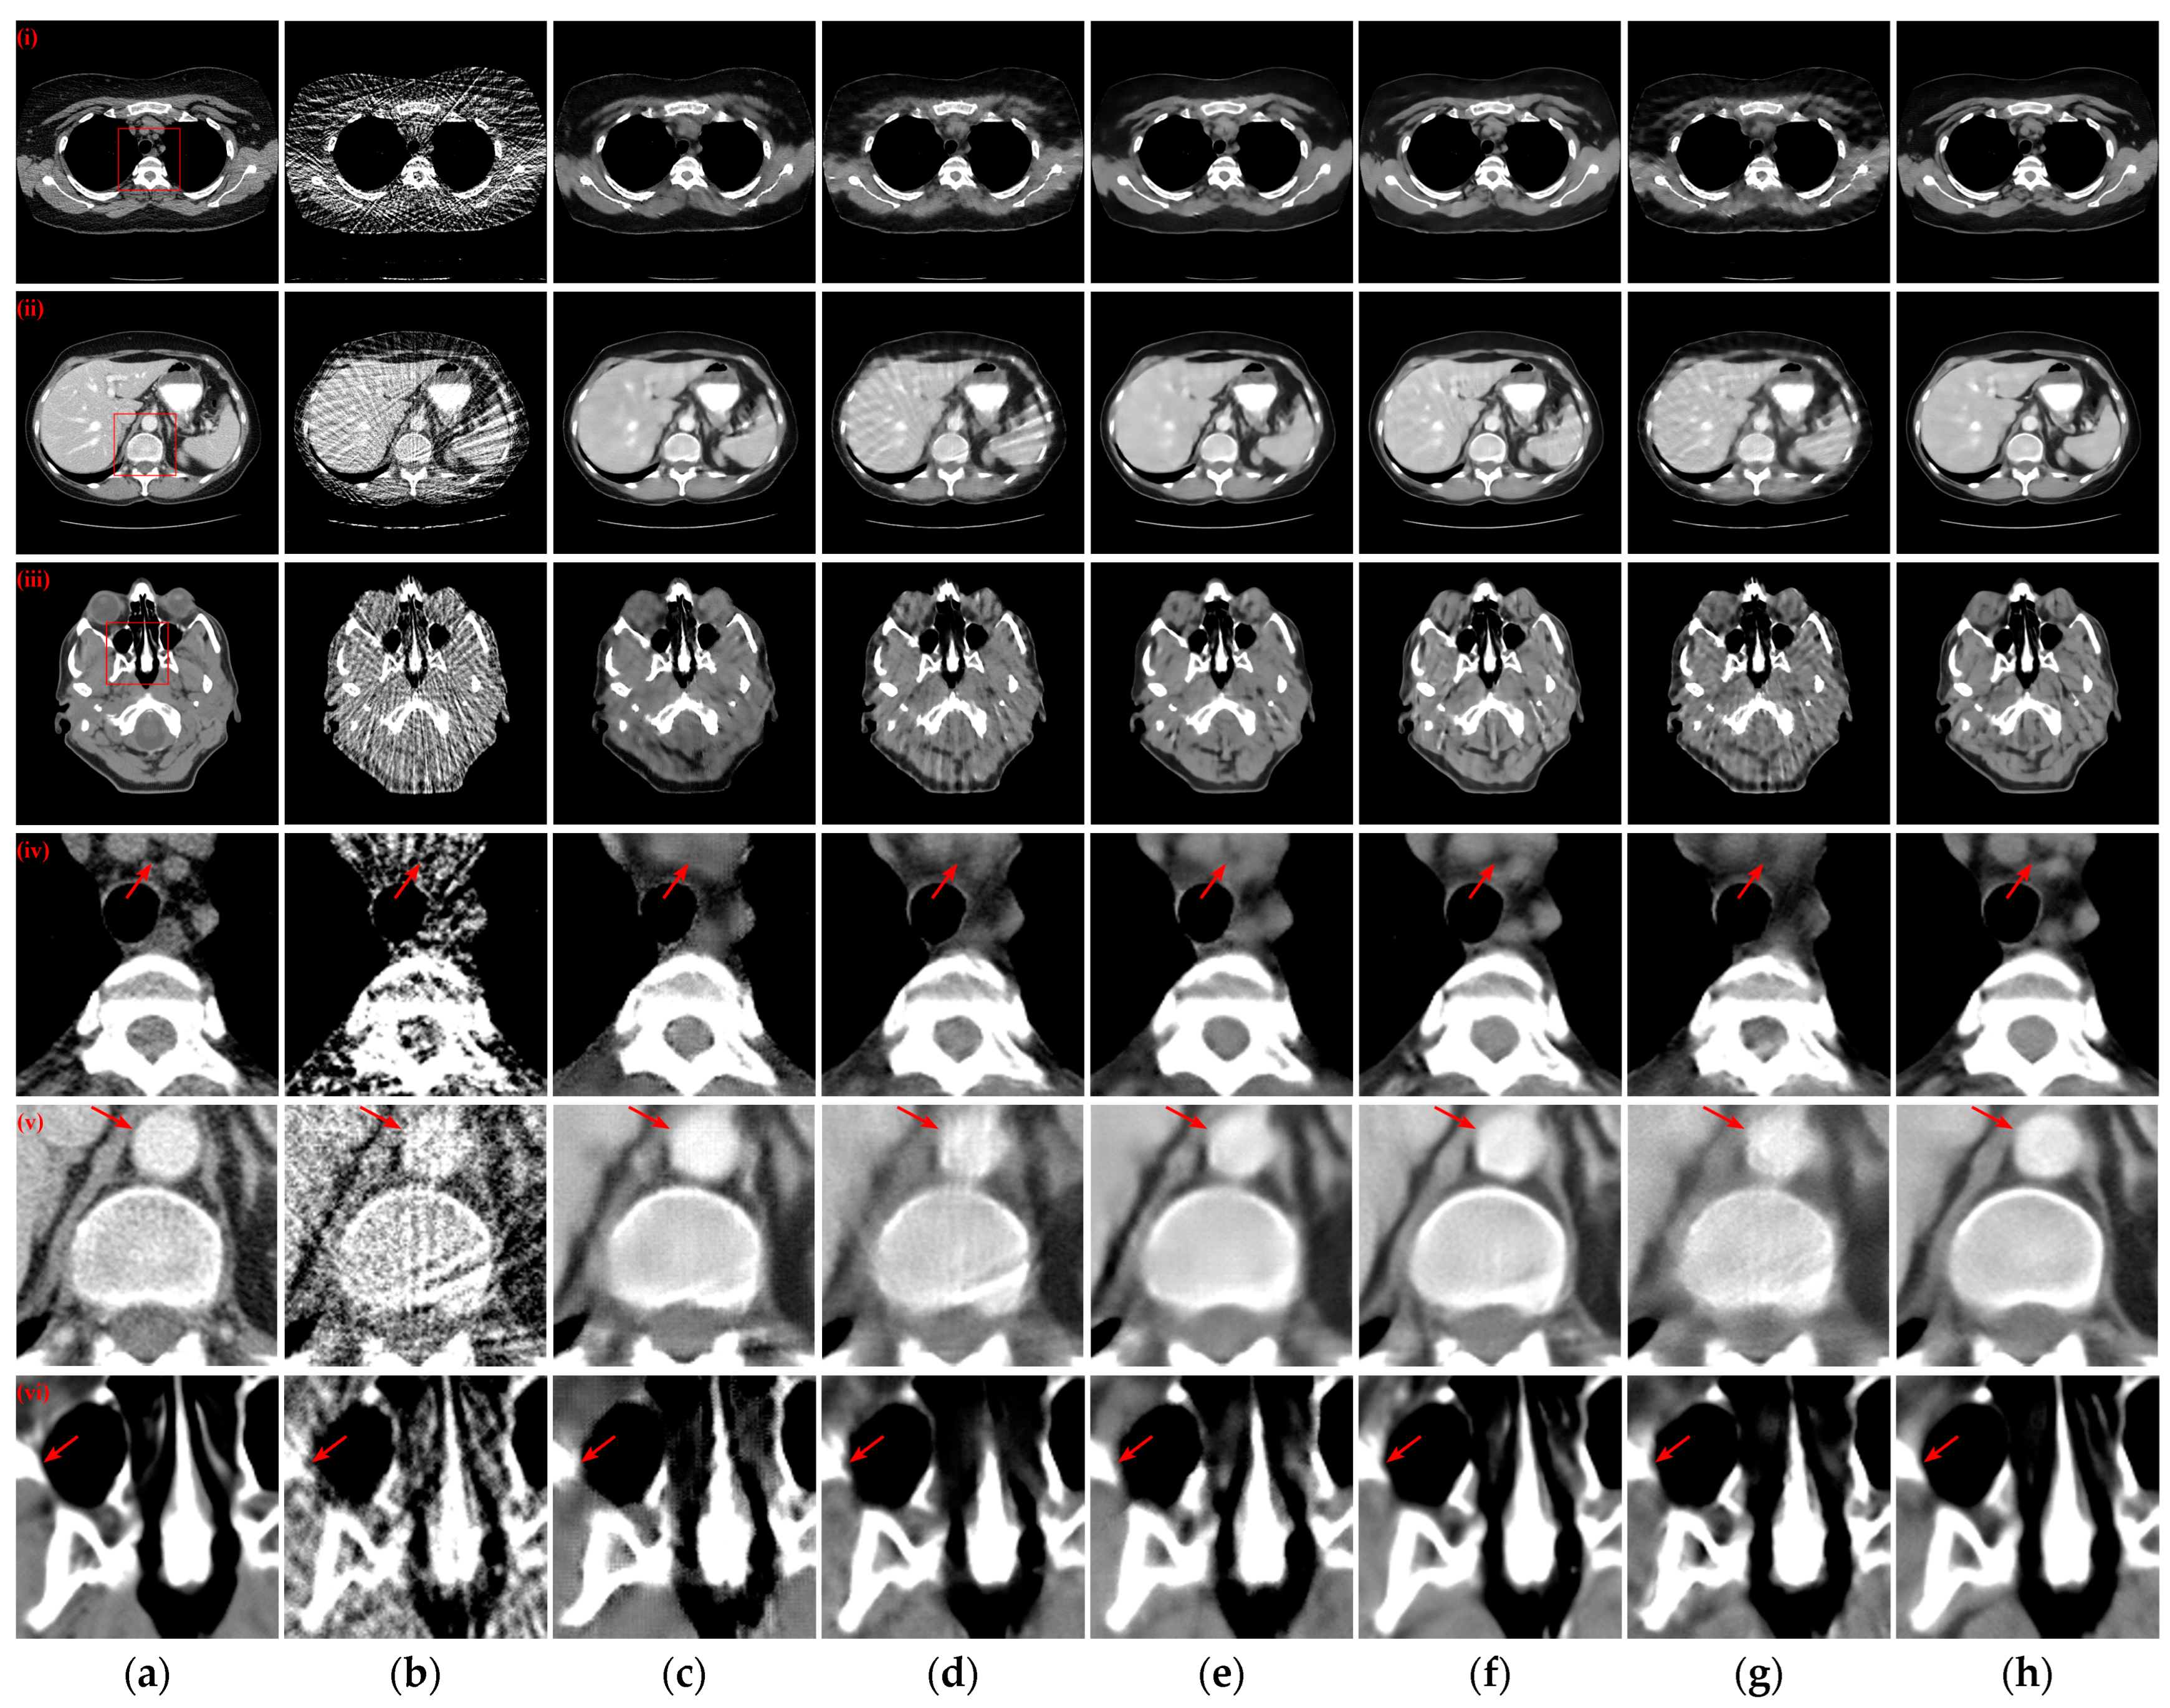

3.2. Qualitative Evaluation